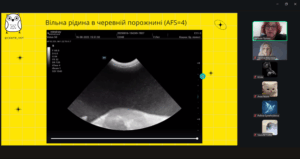

Лектор – Наталія ПРІХНО, яка є кардіологом, лікарем з УЗД даної ветеринарної клініки, розповіла про те, як правильно працювати з УЗД-апаратом, на що звертати увагу під час обстеження котів і собак та які «підводні камені» можуть чекати під час інтерпретації зображень. Було багато корисних порад і реальних випадків з практики — саме те, що найбільше цінують слухачі. Пані Наталія детально пояснила принципи проведення AFAST/TFAST, ключові орієнтири обстеження та їхнє значення у клінічній практиці. Учасники мали змогу ознайомитися з типовими патологіями, які можуть бути виявлені за допомогою цих протоколів, а також з поширеними діагностичними помилками та способами їх уникнення. Окрему увагу було приділено практичним клінічним випадкам, що продемонстрували ефективність AFAST/TFAST у швидкій оцінці стану тварини, прийнятті рішень у невідкладних ситуаціях та моніторингу динаміки стану пацієнта.